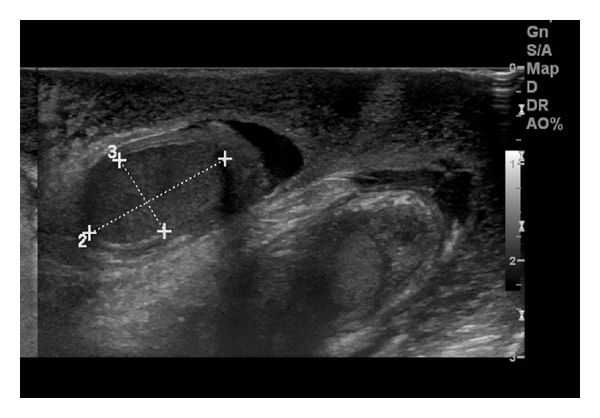

Manuel � un ragazzino di otto anni, che viene portato in Pronto Soccorso per la comparsa da alcune ore di una tumefazione scrotale, accompagnata da una vaga dolenzia localizzata. Non � presente una storia di traumi, febbre o disuria. Obiettivamente lo scroto si presenta iperemico e tumefatto bilateralmente, anche se in maniera asimmetrica, senza interessamento del pene, dell'inguine o del perineo (Figura 1). I testicoli sono palpabili ma tale manovra provoca un vivo dolore; i riflessi cremasterici non sono evocabili e la transilluminazione scrotale risulta negativa. Figura 1. Scroto iperemico e tumefatto, in caso di edema scrotale. Figura 2. Ecografia scrotale: importante ispessimento del tessuto cutaneo-sottocutaneo. Figura 3. Ecografia color-doppler del paziente. Figura 4. Ecografia color-doppler che mostra il �segno della fontana� dato dall�aumento del flusso sanguigno nella pelle scrotale edematosa (da voce bibliografica 1).

Un'ecografia scrotale (Figura 2), richiesta in urgenza per escludere una possibile torsione, ha mostrato entrambi i testicoli in posizione pi� alta che di norma, con volume regolare e vascolarizzazione conservata, senza lesioni focali. Il reperto dirimente � stato per� il riscontro di un importante ispessimento del tessuto cutaneo-sottocutaneo scrotale, con intensa iperemia nella valutazione con il color-doppler che nelle sezioni trasverse disegnava l'immagine di una �fontana scrotale� (Figure 3 e 4), suggestiva di Edema Scrotale Acuto Idiopatico (AISE). La negativit� degli indici di flogosi ha escluso con certezza che potesse trattarsi di una cellulite in fase iniziale.